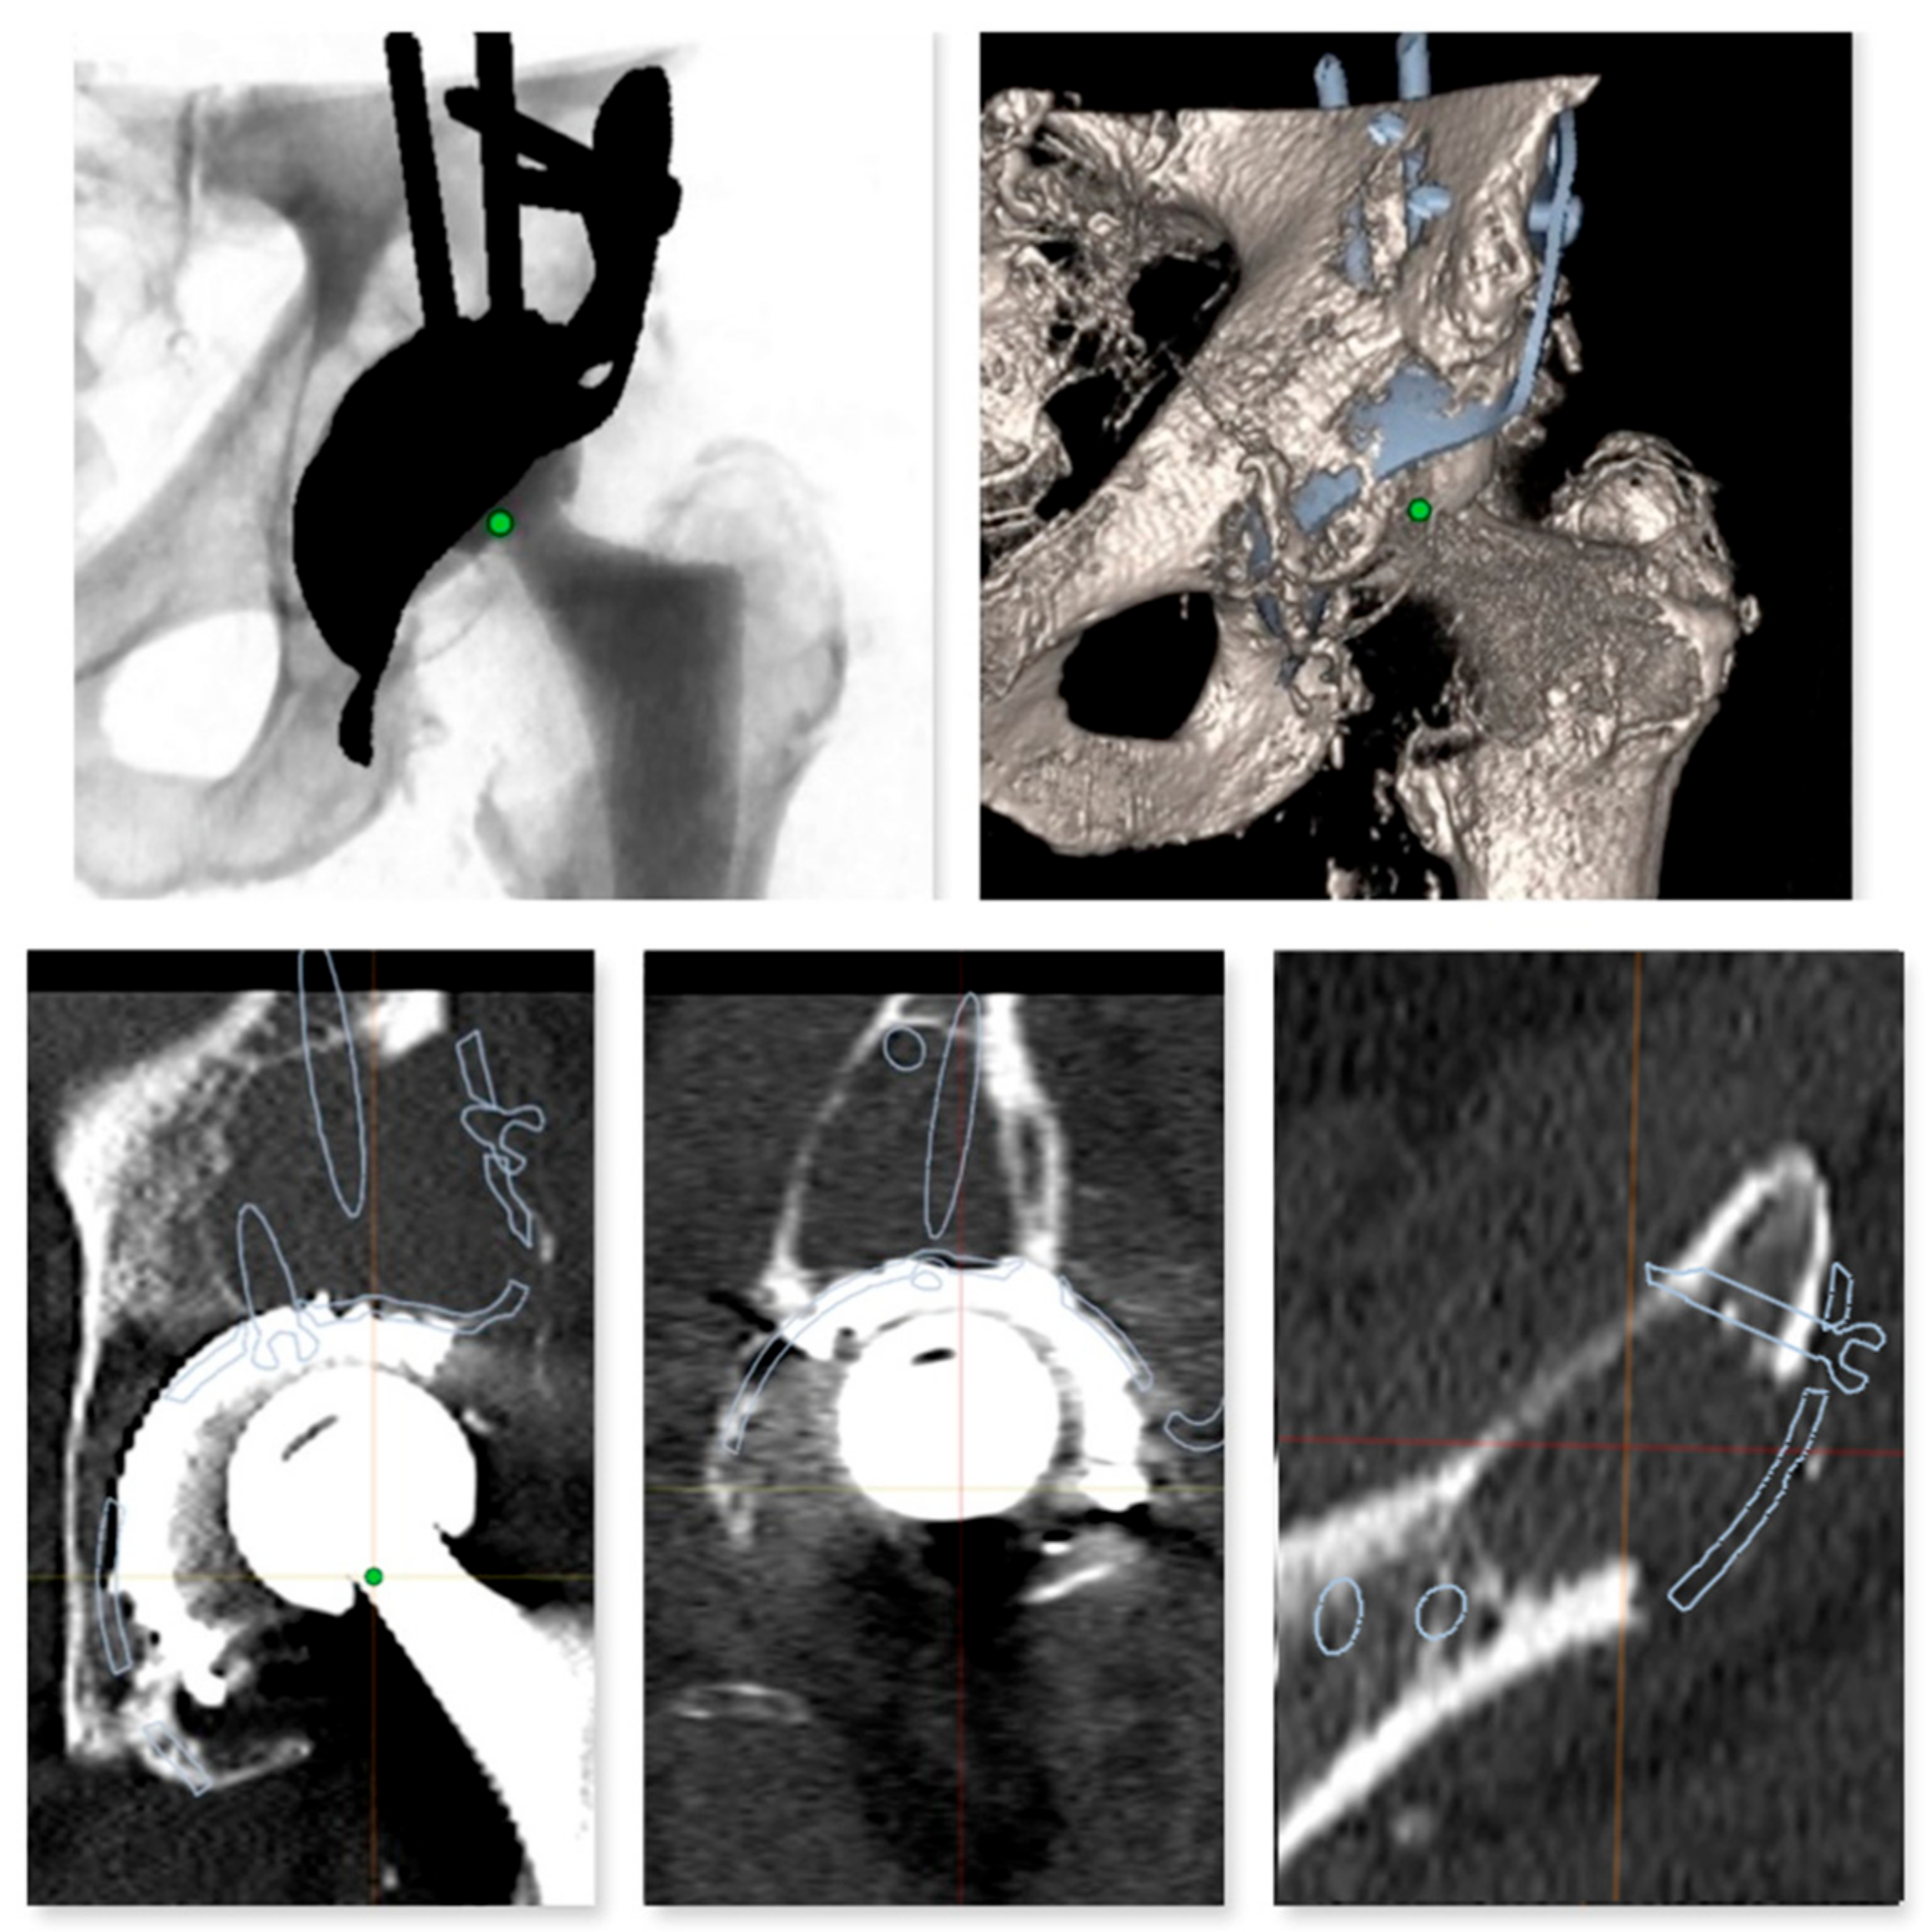

Figure 4. Preoperative planning of the reinforcement cage (Burch Schneider) in the transversal plane of the CT scan. The results of the personalized planning are shown in the center image, indicative of a Burch Schneider reinforcement cage 56 mm in diameter. The upper and lower images show reinforcement cages one size smaller (50 mm; top) and one size larger (62 mm, bottom). In this patient, a 56 mm size reinforcement cage was implanted.